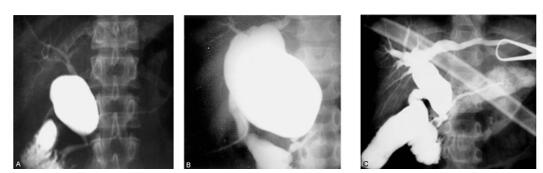

图2 :先天性胆管扩张症的胆管病理形态术中造影

(1) 囊肿型胆管扩张,合并胆管-胰管型胰胆管合流异常

(2) 囊肿型胆管扩张,合并胆管-胰管型胰胆管合流异常

(3) 梭状型胆管扩张,合并胰管-胆管型胰胆管合流异常。

图3:先天性胆管扩张症的肝内胆管扩张

(1)囊肿型胆管扩张,合并肝内胆管扩张

(2)梭状型胆管扩张,合并肝内胆管扩张